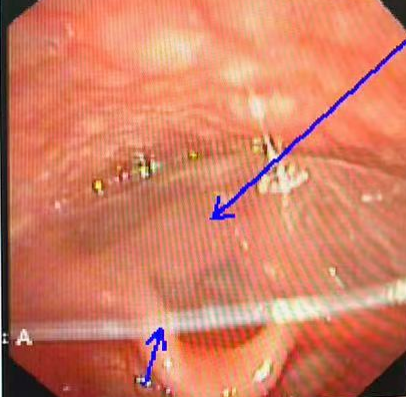

该院儿科急诊邱进东主治医生接诊后,立即携患儿至耳鼻喉科门诊检查并尝试取出异物。耳鼻喉科医生迅速为患儿施行电子鼻咽镜检查,结果令人揪心:一片约2.5厘米×2厘米的硬塑料膜,正嵌顿于患儿下咽部——这一位置被称为呼吸的“咽喉要道”,直接威胁生命。医护人员指出,若不及时取出,塑料膜随时可能移位堵塞声门导致窒息,短短数分钟内即可引发不可逆的脑损伤,甚至危及生命。

鼻咽镜下的塑料硬膜

随即,儿科与耳鼻喉科团队共同制定多套方案,尝试多种路径接近异物:大号鼻咽镜经口操作因患儿反应强烈难以推进;直接喉镜下又因塑料膜透光难以定位……就在抢救陷入僵局时,转机出现。沈玉才主任医师借助经鼻鼻咽镜进行精确定位,同时在直视喉镜辅助下充分暴露患儿咽喉结构。关键时刻,他眼疾手快,精准夹住塑料膜,将其完整取出。异物取出后,患儿呼吸立刻恢复平稳,现场所有医护人员悬着的心终于放下。